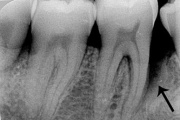

Luukadu agressiivse parodontiidiga patsiendil